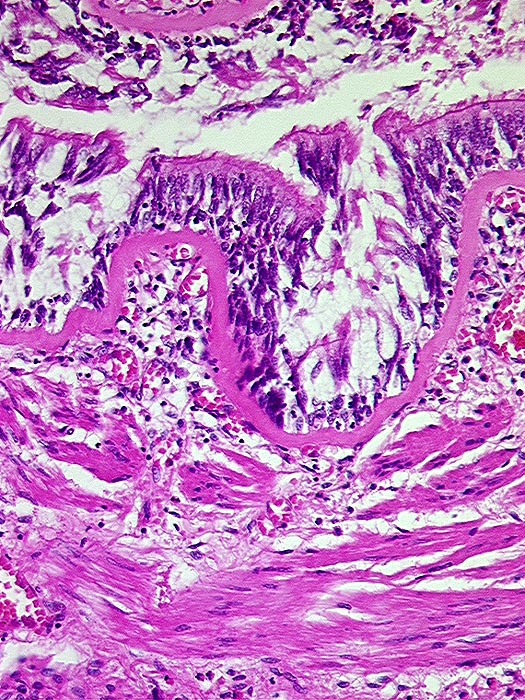

PathoPic ID 544 - Asthma bronchiale

Asthma bronchiale

Entzündung / Reparatur

Lunge

Lunge, Mediastinum mit Thymus

Bronchiolus mit starker Verdickung der Basalmembran und der glatten Muskelschicht.

Tod im Asthmaanfall bei bekanntem Asthma bronchiale.

Histologie